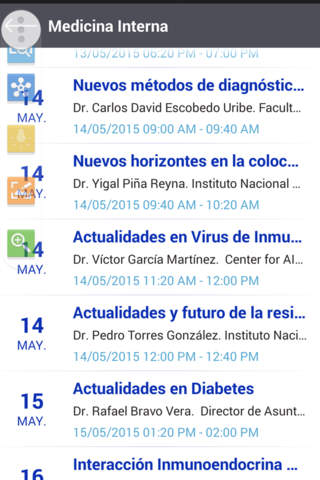

El programa

Una breve semblanza de los ponentes